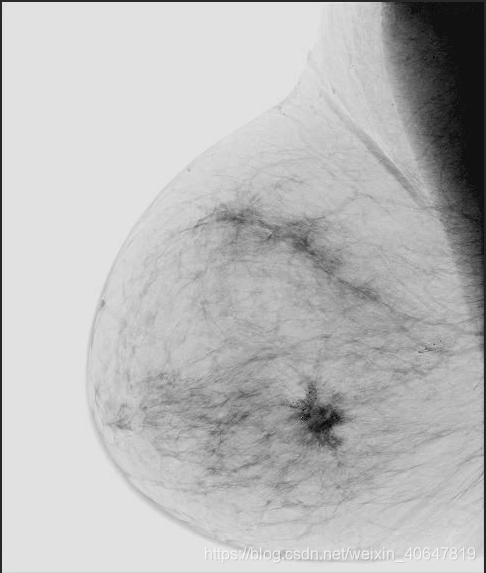

原图:  c=10:

c=10: